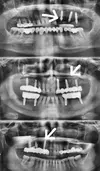

Implant Treatment